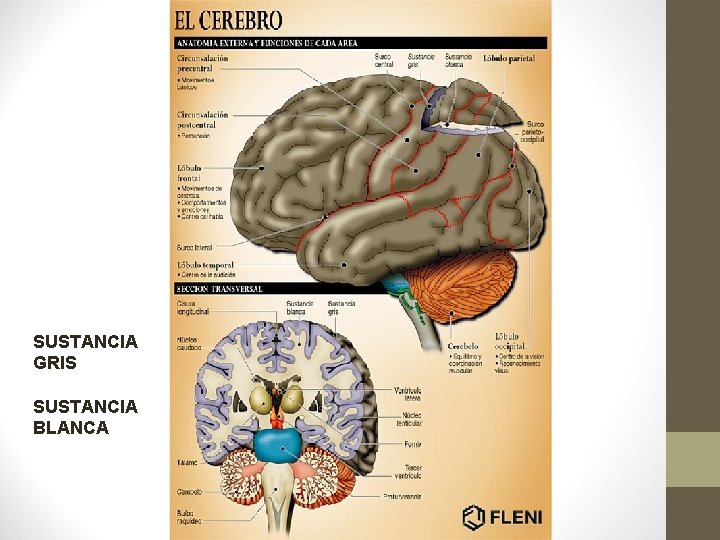

SUSTANCIA GRIS SUSTANCIA BLANCA